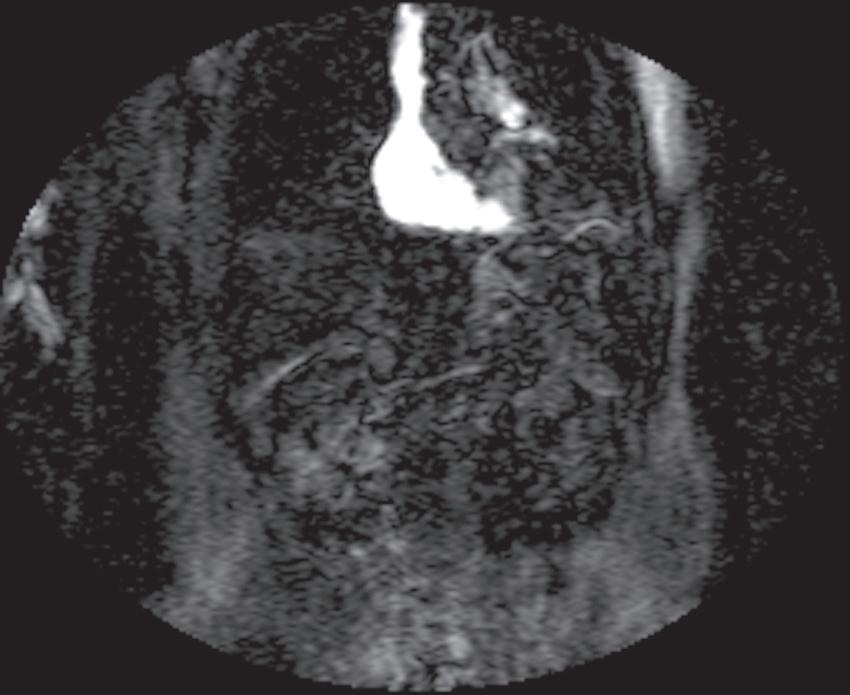

Real-time viewing of contrast transit (Bolus Track, Philips; CARE Bolus, Siemens; SmartPrep, GE; VisualPrep, Toshiba) involves careful monitoring by the technologist of serial large field-ofview (FOV) GE images after administration of the entire bolus of contrast (see Fig. 1.17). Transit of gadolinium through the superior vena cava (SVC) into the right heart through the pulmonary circulation and from the left heart into the aorta is portrayed on the monitor cinegraphically. With impending arrival of contrast into the abdominal aorta, the technologist instructs the patient to suspend respiration in preparation to acquire the arterial phase images. Portal phase images (or

FIG. 1.17 Example of Bolus Track timing sequence to initiate the dynamic acquisition. Selected serial coronal large field-of-view gradient-echo images obtained immediately after the intravenous administration of gadolinium (A–D) reveal the inflow of gadolinium into the superior vena cava (SVC; A), the right ventricle (B), through the pulmonary outflow tract and into the pulmonary arterial system (C), and into the thoracic aorta, down the abdominal aorta (D).